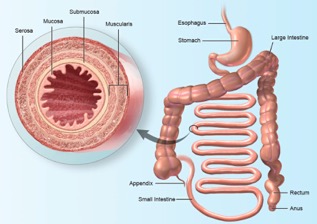

4. Sistem Pencernaan / Digestif

Sistem yang menjadi tunggak utama dalam memahami pelbagai jenis penyakit yang terkait pada pemakanan. Sistem yang padat dengan pelbagai organ dalaman yang membentuk jalur pencernaan daripada saat masuknya sesuatu makanan dan minuman kedalam tubuh, penyerapan nutrisi dan zat yang diperlukan oleh tubuh hinggalah kepada pembuangan sisa yang tidak diperlukan oleh tubuh. Memahami sistem ini akan dapat membantu para perawat dalam mendiagnosa penyakit yang berkisar pada bahagian perut (abdomen) dengan lebih tepat dan bersandar dengan dalil ilmiah.